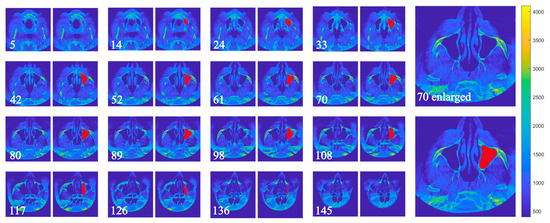

Retrospective Evaluation of Maxillary Sinus Volume Changes Following Bone-Anchored Midface Distraction Osteogenesis in Cleft Patients: A Case–Series Study

Background/Objectives: This study retrospectively evaluated maxillary sinus volume changes and linear changes in the craniofacial region after Le Fort I distraction osteogenesis using a rigid external distraction system. Methods: Ten patients who underwent LeFort 1 distraction osteogenesis between 2012 and 2025 [...] Read more.

Background/Objectives: This study retrospectively evaluated maxillary sinus volume changes and linear changes in the craniofacial region after Le Fort I distraction osteogenesis using a rigid external distraction system. Methods: Ten patients who underwent LeFort 1 distraction osteogenesis between 2012 and 2025 were included in the study. Computed tomography scans and lateral cephalograms were obtained before and 12.3 ± 6.98 months after the surgery. The associated volumes of the maxillary left and right sinuses were subsequently measured using the semiautomatic segmentation method in the ITK-SNAP software. Linear measurements of the sinuses and cephalometric analysis were performed before and after the distraction. Results: The Wits appraisal (distance between perpendicular lines drawn from point A (on the maxilla) and point B (on the mandible) to the occlusal plane) presented an increase of 9.33 mm ± 7.93 mm, corresponding to an increase in the ANB angle by 9.88° ± 5.35°. There were statistically significant increases in the total sinus volume, by 3965 mm3 ± 5456 mm3 (n = 10, p = 0.047), and in the single maxillary sinus volume, by 1983 ± 2889 mm3 (n = 20, p = 0.003). A significant increase in height was also observed, with a mean value of 4.46 ± 2.94 mm (n = 20). Conclusions: Extraoral bone-anchored midface distraction osteogenesis led to increases in single sinus volume, total sinus volume and sinus height in the cleft cohort, resulting in improved maxillary retrusion and profile. However, the study group was small and non-uniform with different follow-up periods, indicating a need for further studies with larger, more homogenous cohorts. Full article